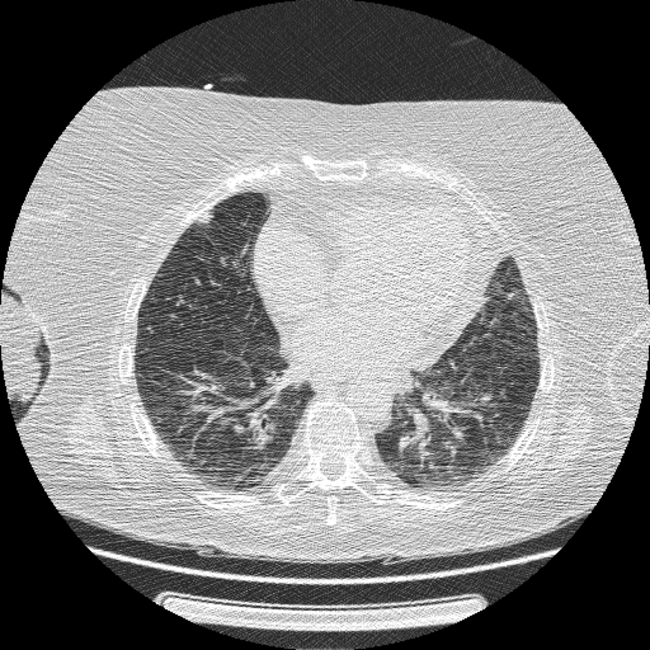

【EIRL Chest CTによる表示例】

2. 低線量CT

低線量CTについて

通常のCTに比べ、被検査者に与える被ばく量を軽減することが可能です。一方、撮影される画像は、通常のCTに比べて質が低下する傾向にあり、読影診断の難易度が高まると言われています。